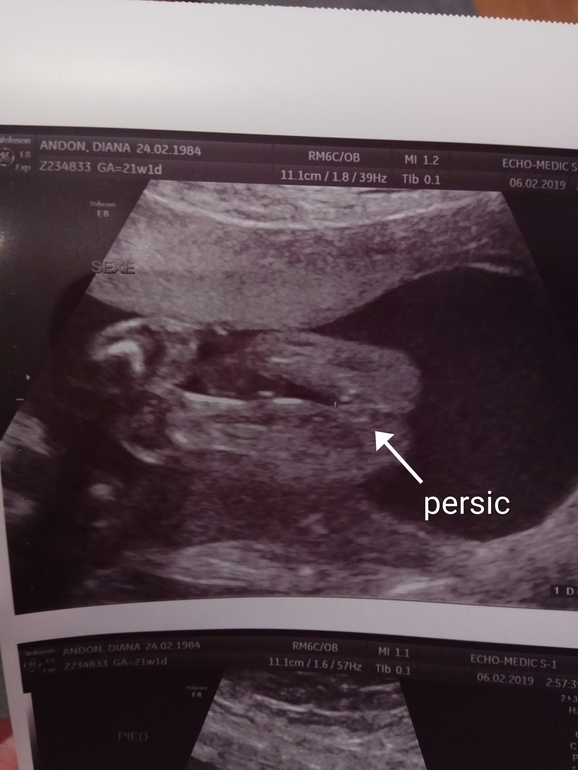

Потом говорит что вот смотрите тут половые губы, и я рассплылась от счастья, столько радости при виде женской письки еще никогда не истпытывала😂😂😂

Хорошо что сделали отличное фото причинного места и сомнений не осталось))

Поздравляю с дочечкой))) я вот до сих пор не верю, хотя тоже фоточку персика дали😁